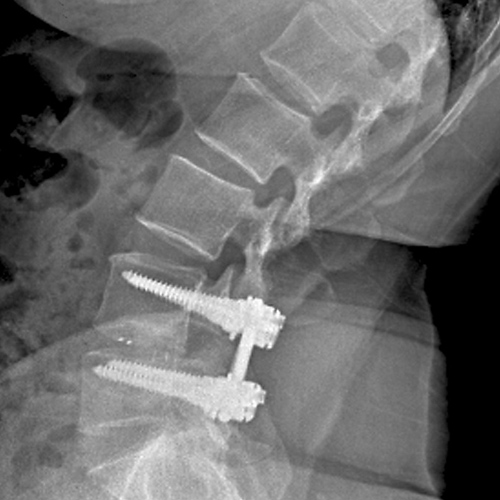

척추관 협착이나 기타 변형으로 인해 불안정한 척추를 스크류로 안정화시켜 수술 후 조기 보행과 유합율을 높여 줍니다.

협착증이 있는 부분에 요추 후궁절제술로 척수신경을 충분히 풀어 준 다음에 척추의 불안정증을 교정하기 위하여 기구(스크류)를 이용하여 척추를 고정하는 수술입니다.

나사못과 금속 기구를 사용하여 불안정한 척추 분절을 단단하게 고정하고 유합시켜, 척추의 안정성을 영구적으로 확보합니다.

불안정하거나 퇴행된 척추 마디의 움직임을 제거하여, 해당 부위에서 발생하는 만성적인 통증을 근본적으로 해소하는 데 가장 효과적입니다.

나사못 고정과 함께 신경을 압박하는 구조물(인대, 뼈 등)을 충분히 제거하여 신경 통로를 넓히는 감압 효과를 극대화합니다.